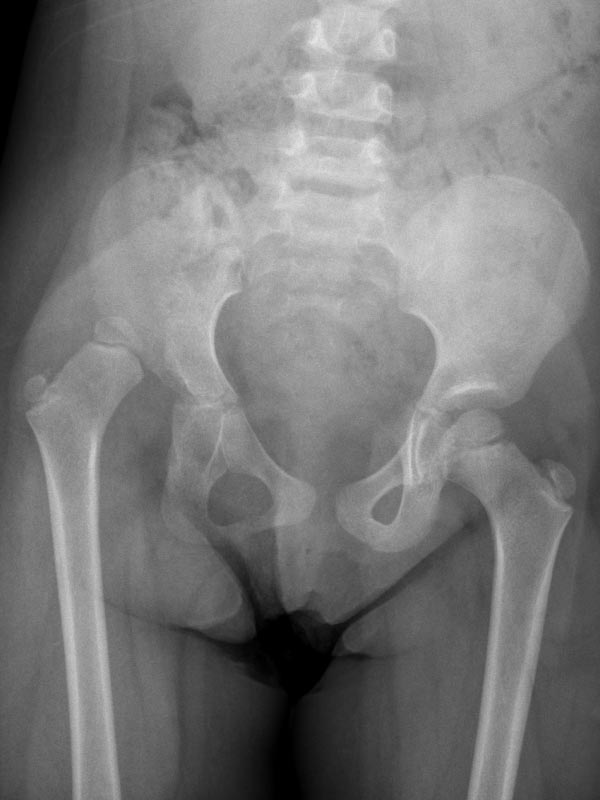

Caso No. 3 - Displasia de cadera derecha con luxación

Preoperación

Posoperación

Displasia de cadera

Diagnóstico: Displasia de cadera derecha con luxación

Tratamiento quirúrgico realizado: reducción abierta, acetabuloplastía y acortamiento femoral

Operada a los 5 años por no diagnosticarse antes, ahora tiene una cadera derecha útil